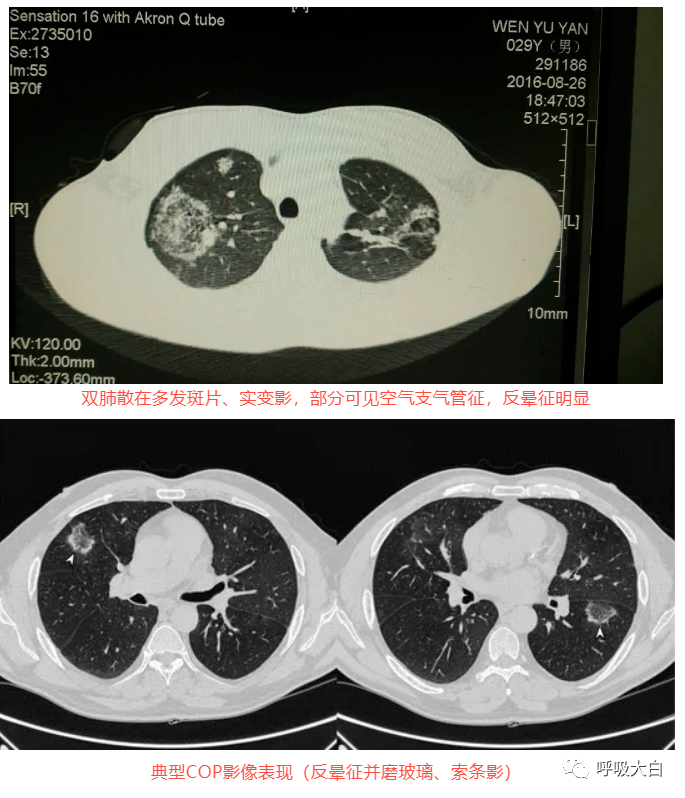

反晕征是一种特殊的胸部 CT征象,表现为环状高密度影围绕着中央密度较低的肺部阴影。起初认为,反晕征为隐源性机化性肺炎的特征性的征象;但此后被报道见于多种其他疾病,如肺副球孢子菌病、肺淋巴瘤样肉芽肿病、肺结节病、侵袭性肺真菌病、活动性肺结核及肉芽肿性多血管炎( 原韦格纳肉芽肿),亦可见于继发于感染或胶原血管病的机化性肺炎。

在隐源性机化性肺炎,反晕征中央的磨玻璃影的病理基础是肺泡间隔的炎症和细胞脱屑及少量终末气腔内的肉芽组织, 而外周的环状高密度影则对应远端气腔( 细支气管、肺泡管、肺泡腔) 内的纤维机化。表现为反晕征的结节病,外周的环状高密度影对应着多发的肉芽肿。肺隐球菌病则对应着肉芽肿性炎,PAS 染色可见着红色荚膜的隐球菌。肺结核的 CT环状高密度影对应的病理是上皮样肉芽肿,伴或不伴干酪样坏死,抗酸染色阳性或阴性。

在肉芽肿性疾病,其外围的环状高密度影不光滑, 而在非肉芽肿性疾病,外围的高密度影则较为光滑,此特征可用于初步判断病理性质。

隐源性机化性肺炎(COP):